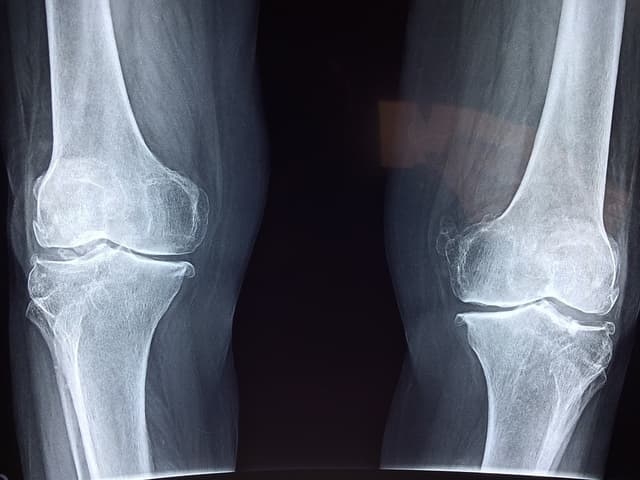

Paget’s Disease

Paget’s disease is a chronic bone disease of the skeleton. In a healthy bone, a process known as remodeling begins to remove old parts of bone and replace them with fresh bone. Paget’s disease causes the new, fresh bone to grow abnormally in shape and be weak and brittle. It is a disease that more often affects older individuals and can occur in the legs, spine, pelvis and skull.

• Leg: When bones become weak, they can start to bend, which can cause the individual to become bow-legged. Misshapen or enlarged bones in the legs can create added stress in nearby joints, which can lead to osteoarthritis in the hip or knee.